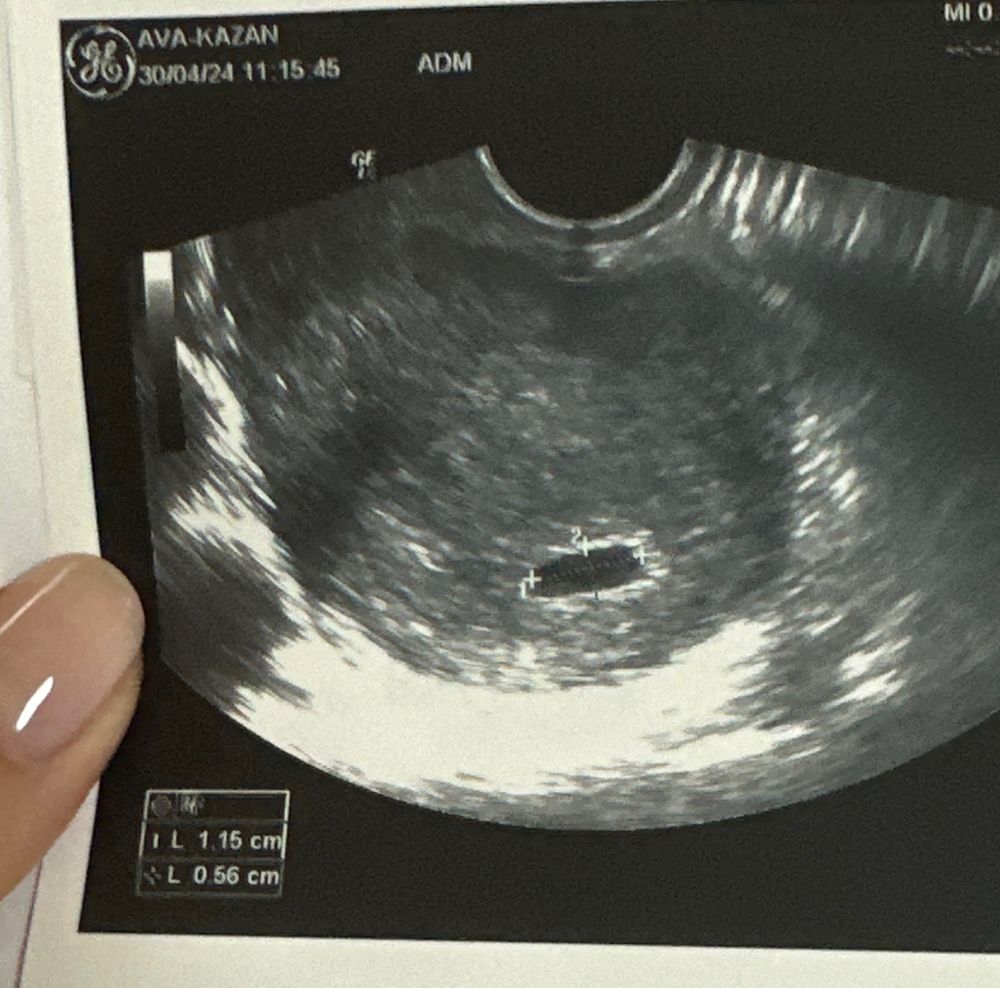

LA VE, вот Изображение

Альфия, вот такие замеры Изображение

Не видно эмбриона На какой день после переноса увидели ПЯ??